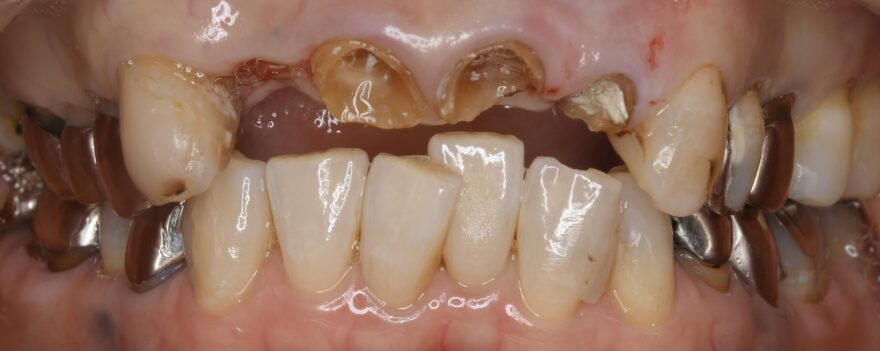

治療前の口腔内写真

前歯4本をインプラントで再建する必要がありました。